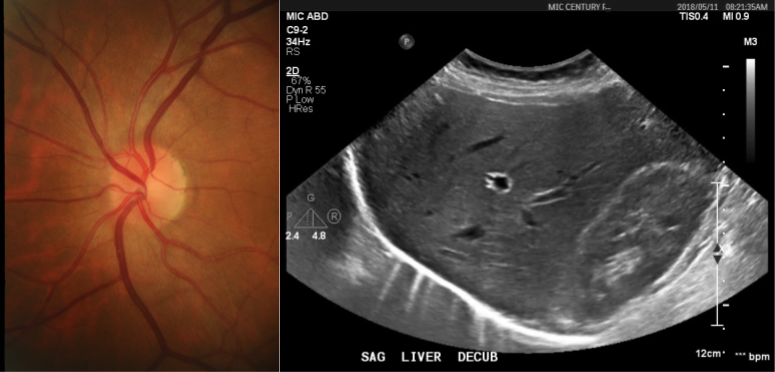

3.1 Example: Hip dysplasia

Developmental dysplasia of the hip is a deformity of the hip joint at birth that affects close to 3% of infants [14]. Ultrasound imaging is one way to diagnose this condition. To do so, the medical expert measures the angle α𝛼\alpha between the acetabulum and ilium, and the coverage c𝑐c (ratio between the two segments d1subscript𝑑1d_{1} and d2subscript𝑑2d_{2}); as shown in Figure 1 [8, 13, 14].

Refer to caption

Figure 1: (Left) Typical 2D ultrasound image of the hip. (Right) The structures of interest: the acetabulum, the ilium and the femoral head, as well as the angle between the acetabulum and ilium (α𝛼\alpha), and the information for computing the coverage: c=d2d1+d2𝑐subscript𝑑2subscript𝑑1subscript𝑑2c\ =\ \frac{d_{2}}{d_{1}+d_{2}}